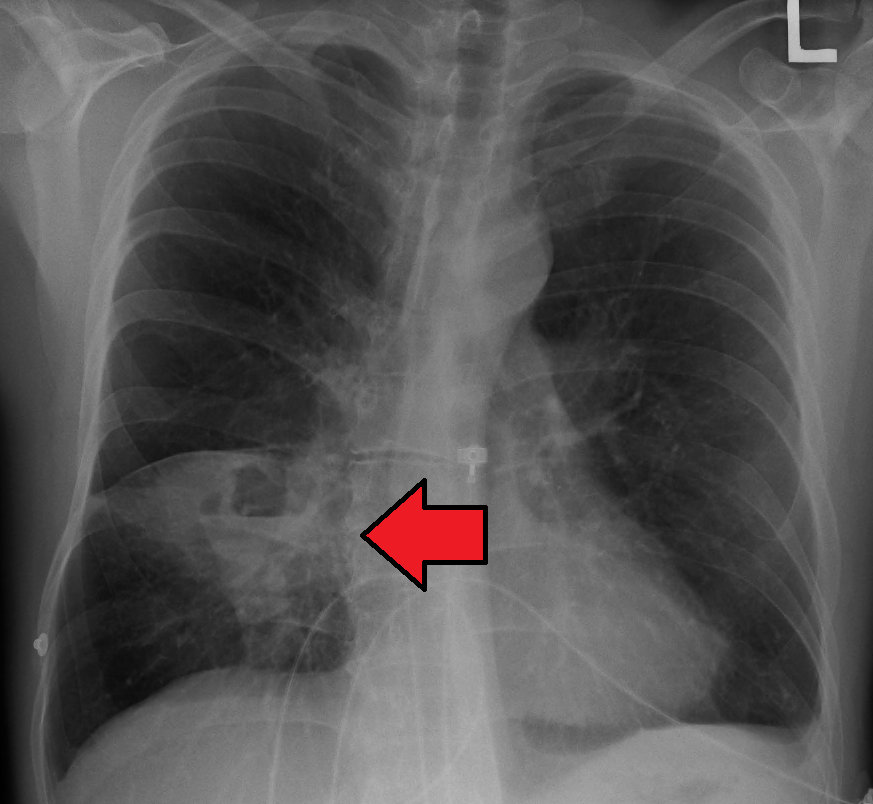

폐 잡음은 특별한 것은 없다. 흉부 엑스레이에서 폐 부분에 단발성 구형 백색 음영이 관찰되며, 구형 음영 내부는 고름으로 채워져 있어 수평선이 관찰될 수 있다. CT 스캔으로 확진할 수 있다.[1]

5. 1. 영상 검사

폐농양은 종종 편측에 나타나며, 누워있을 때 중력에 의해 영향받는 상엽의 후방 분절과 하엽의 첨단 분절을 침범하는 단일 병변이다. 공기-액체 경계면(air-fluid level)의 존재는 기관지로의 파열이나 드물게 가스 형성 미생물의 성장을 의미한다.[1]흉부 엑스레이에서는 폐 부분에 단발성 구형 백색 음영이 관찰된다.[1] 구형 음영의 내부는 고름으로 채워져 있으며, 수평선이 관찰될 수 있다.[1] CT 스캔으로 확진할 수 있다.[1]

폐 잡음은 특별한 것은 없다. 흉부 엑스레이에서 폐야에 단발성 구형 백색 음영을 관찰한다. 구형 음영의 내부는 고름으로 채워져 있으며, 수평선을 관찰할 수 있다. CT 스캔으로 확진할 수 있다.